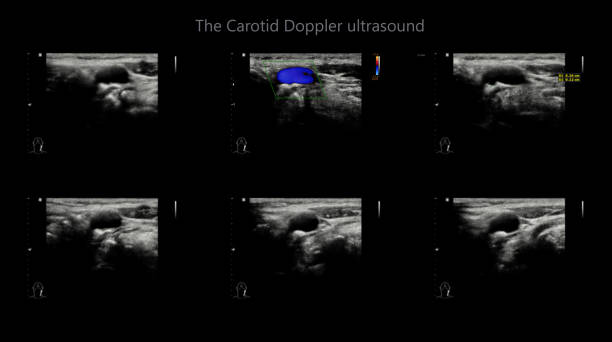

경동맥 초음파 검사의 원리

경동맥 초음파 검사는 초음파 기계를 사용하여 경동맥의 상태를 확인하는 검사입니다. 이 검사는 무해하고 비침습적이며, 빠르게 수행할 수 있어 환자에게 불편함을 주지 않습니다. 검사 과정은 다음과 같습니다.

경동맥 초음파 검사로 알수있는병 - 검사 결과 해석

검사 결과를 해석할 때, 의사는 다음 사항을 고려합니다.

- 경동맥의 크기와 형태: 경동맥이 충분히 넓고 매끄럽게 유지되는지 확인합니다.

- 혈류 속도: 혈액이 경동맥을 흐르는 속도를 측정하여 혈액순환에 이상이 없는지 확인합니다.

- 혈액 응고물질의 존재: 콜레스테롤과 혈액 응고물질이 경동맥 벽에 쌓여 있는지 확인합니다.